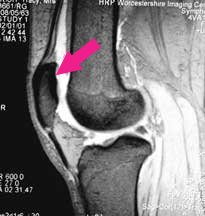

Here is an MRI scan, looking at the knee bones from the side, and where contrast has been reversed so that the bones are dark. You can recognise the rounded ends of the femur and the flattened top of the tibia.

The patella (red arrow) is quite peculiar. It is located right in the middle of the tendon of the quadriceps muscle, the muscle which forms most of your 'lap'- the tendon being the bit at the lower end where the muscle attaches to the tibia. From inside the joint only the undersurface of the patella is visible. The tendon above and below lies ouside the joint lining and cannot be seen.